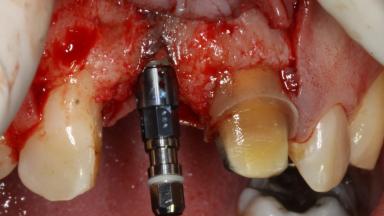

The patient presented with a failing tooth-supported fixed dental prosthesis with cantilever extension replacing the right maxillary central incisor. His chief presenting complaint was poor esthetics, in particular the dark discolored margin around the abutment tooth, the maxillary left central incisor. He reported a history of trauma at a young age, which necessitated the replacement of his maxillary right central incisor as well as root canal therapy of the adjacent left central incisor. The existing prosthesis had been in situ for over 20 years. The initial periapical radiograph displayed good proximal bone levels at the adjacent teeth and a wide incisive canal, which was a concern. The left central incisor presented a very wide root canal treatment with compromised radicular dentin thickness, which was a consideration in the decision between a new tooth-supported fixed dental prosthesis vs. an implant-supported prosthesis. After a lengthy discussion on the risks and benefits of both treatment options, the patient decided on a single-tooth implant replacement.